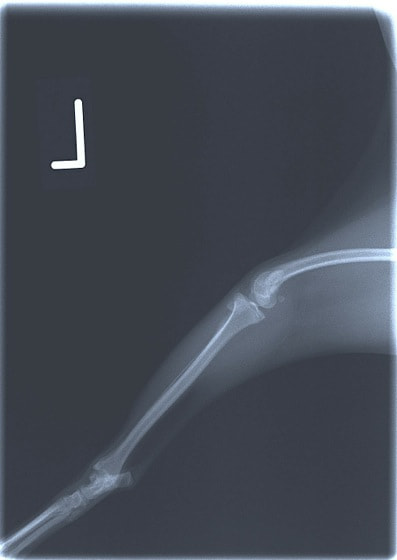

■ 症例24 キャバリア 7か月

左右膝蓋骨内方脱臼(左:グレードⅣ 右:グレードⅢ)

以前から左右後肢の跛行が認められ、整形外科学的検査・レントゲン検査により左右の膝蓋骨脱臼が認められた。症状が重度である左膝の膝蓋骨脱臼整復術を行った。外科手技は縫工筋及び内側広筋の解放、脛骨粗面の外側転位、滑車ブロック形造溝術、内外側関節方の縫縮を実施した。術後一か月時点で、左の膝蓋骨は安定しており経過は良好である。

本症例は成長期における重度の膝蓋骨脱臼であり、術後の再発の可能性もあるため、経過をしっかりと観察していく必要がある。また、今回手術を実施していない右膝に関しても経過を観察し、手術を検討していくこととする。